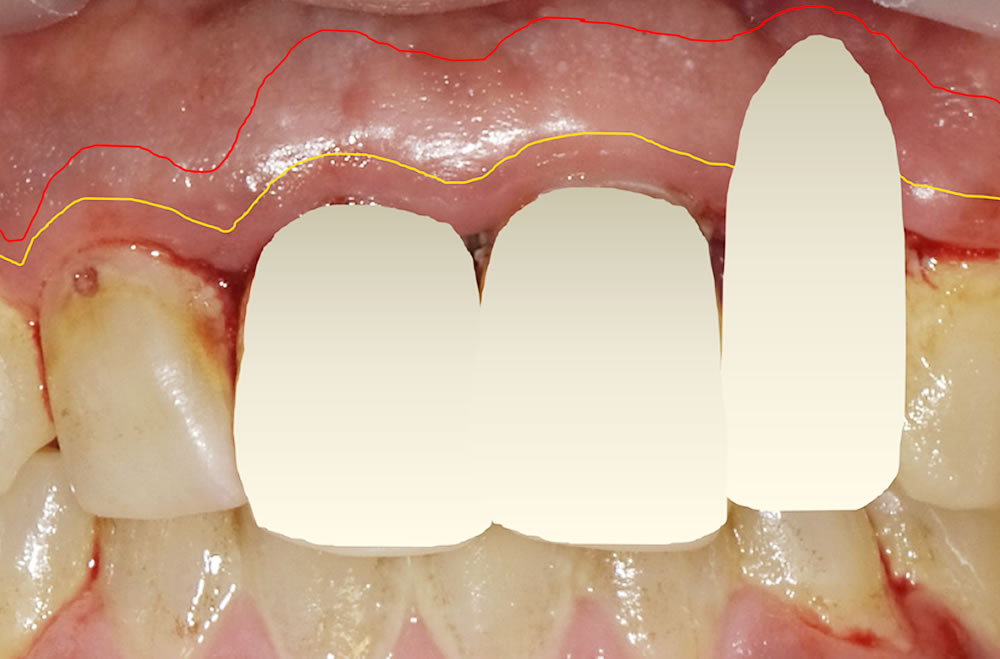

歯周病で歯を欠損した箇所をブリッジで治療した症例

▼こちらの患者様は、前歯がグラグラして抜け落ちたとのことでご来院されました。

歯周病が重度に進んでいたのでしょう。歯周病は進行すると歯を支える頭蓋骨が溶け、歯の動揺が少しずつと大きくなり、最終的に抜け落ちてしまいます。骨が溶けていくのに痛みはありませんので、抜けた部分以外にも一度全体を検査していくことにしました。

【初診時の口腔内】

患者様に話を聞くと、今までに虫歯治療で歯を削った記憶はほとんどないとのことでした。確かに、前歯以外は虫歯治療の痕跡がありません。しかし、歯周病の検査をすると問題点が見えてきました。※写真でもお分かりいただけるように、歯周病検査時に歯ぐきからの出血が確認できました。

- 歯周病治療により前歯2本の被せ物と歯肉とのラインに不調和ができている点。

- 前歯2本は被せ物をやり替えたいとの希望があった点。

上記の3点から、前歯2本+欠損した歯の3本分のブリッジで奥に伸ばす設計(延長ブリッジ)としました。もちろんこれにも欠点がないわけではないので、十分に説明し理解をいただいた上で治療を開始しました。

【既存の被せ物を除去】

治療の方針が決まったので、従来の被せ物を丁寧に取り外し、仮歯に置き換えて歯肉の経過を半年ほど見ました。